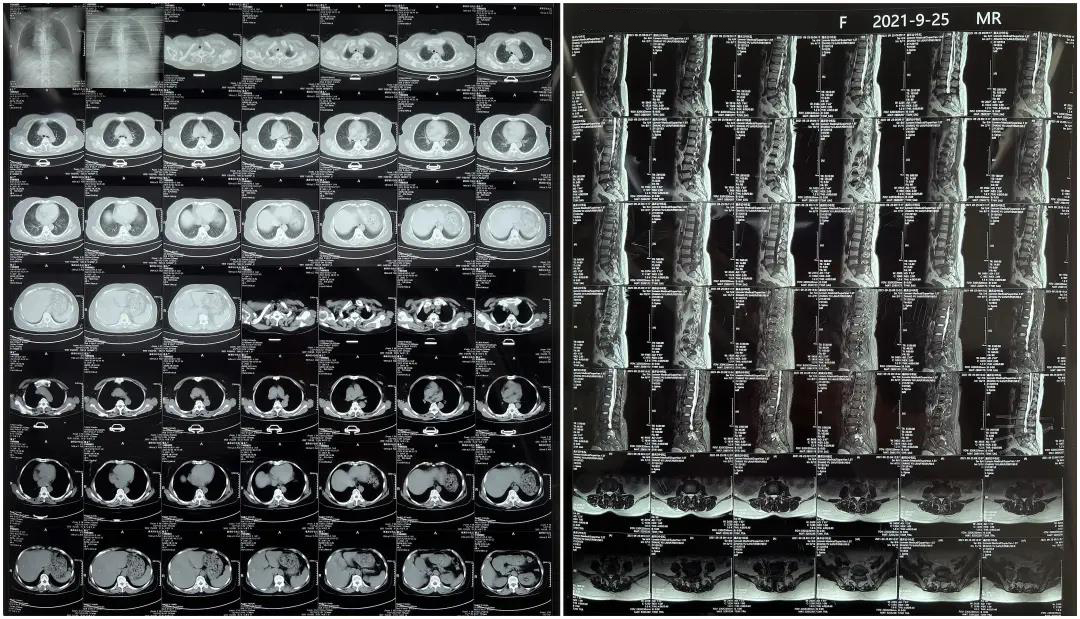

患者1:女性,56岁,L5/S1椎间盘椎板减压+钉棒固定术

患者下腰部疼痛,活动受限,伴有左下肢疼痛5年,久站或弯腰干活时疼痛加剧,卧床休息后疼痛症状缓解,近一个月情况加重,需行椎板减压+钉棒固定术。

术前患者核磁共振图像

显示L3/4、L4/5椎间盘突出,L5-S1水平椎管内占位